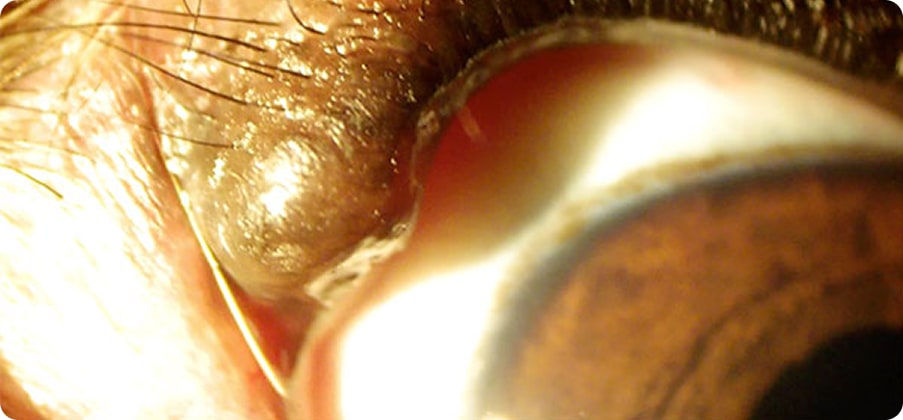

眼瞼には角膜の保湿するために油を分泌するマイボーム腺があり、マイボーム腺が腫瘍化する事が多いです。他にも黒色 腫など悪性の事もありますので発見した場合は早めの受診をお勧めします。

マイボーム疾患には腫瘍、睫毛重生、マイボーム腺炎等があります。マイボーム腺炎を引き起こすと外側もしくは内側に反るように腫れてしまう事が特徴です。細菌等が原因である事がある ため、抗生剤等の治療が必要です。